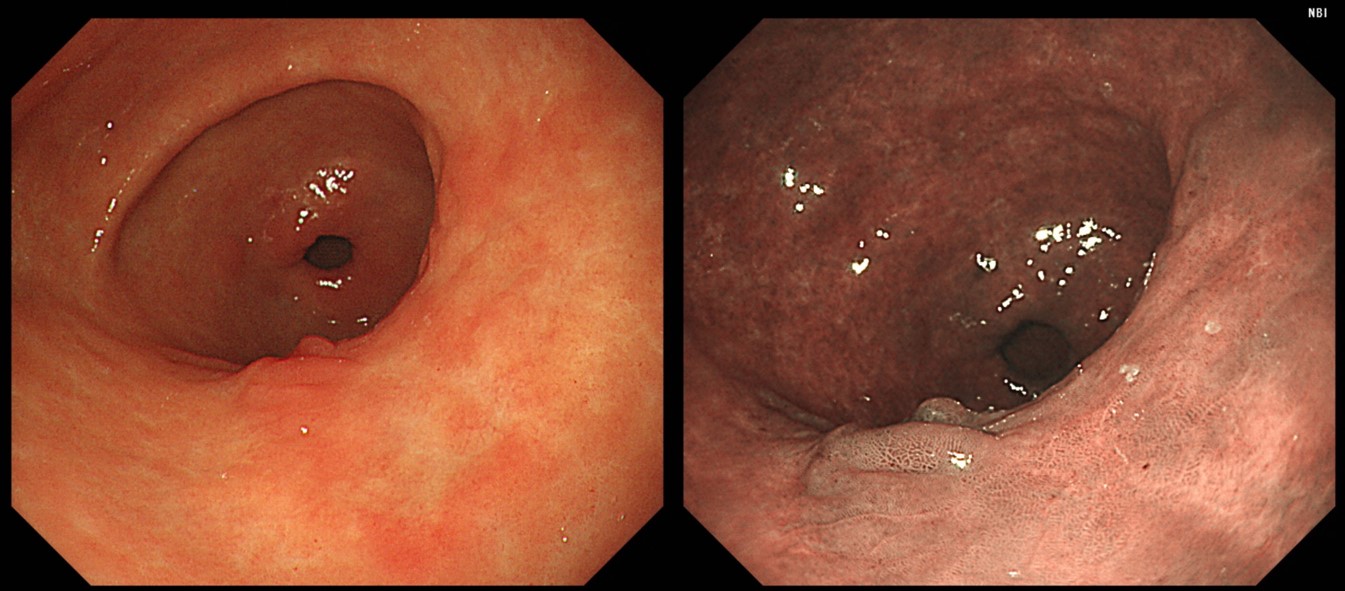

¿¹Á¦ 3 (Âü°í: EndoTODAY Á¶±âÀ§¾Ï ¾ÆÆ²¶ó½º) - 'EndoTODAY À§³»½Ã°æ »ðÀÔ°ú °üÂû' Áõ·Ê 04 (118ÂÊ)